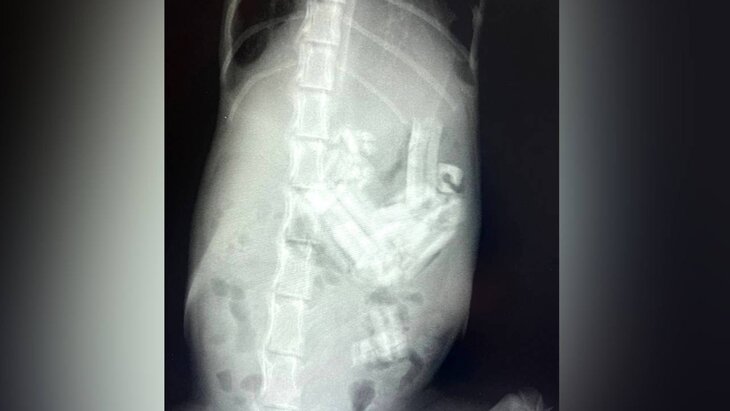

Владельцы четырехмесячной кошки обратились за помощью в ветклинику "Вешняки". Там врачи, отправив питомца на рентген, обнаружили 20 кусков проглоченной резинки в ее желудка и еще два – в 12-перстной кишке и тонком отделе кишечника.